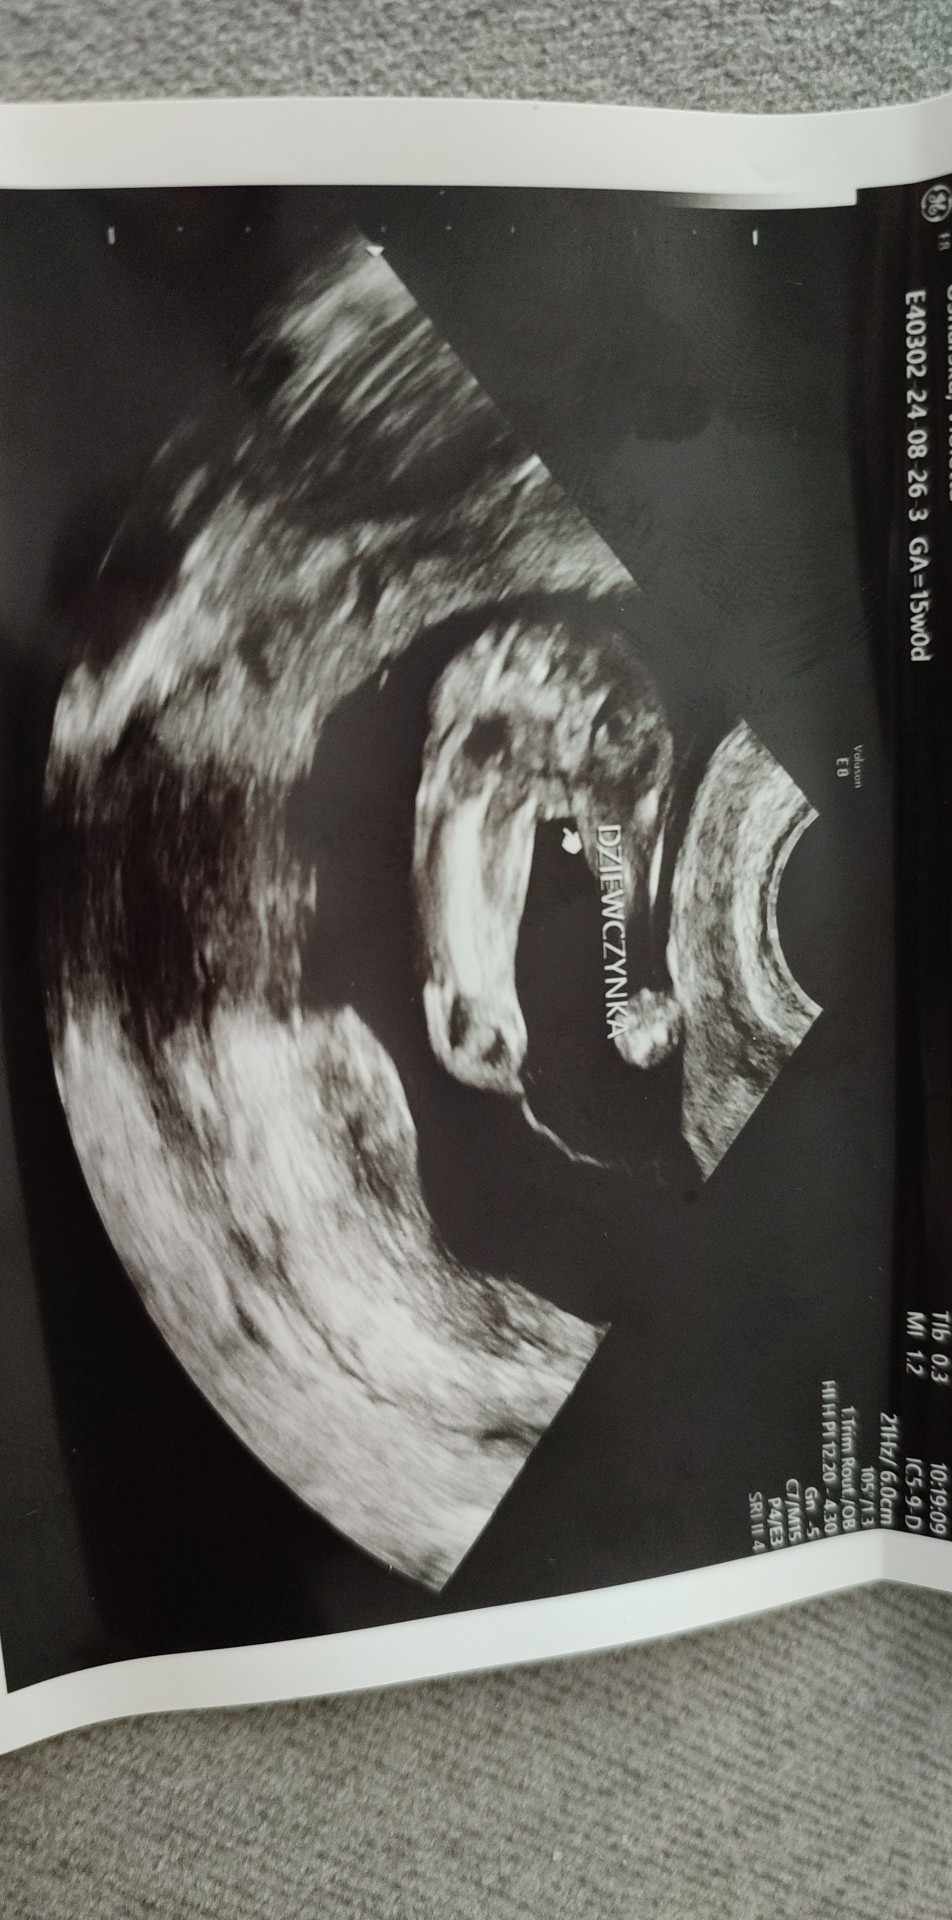

Płeć dziecka w 15tc

Hej dziewczyny czy tu widać że będzie dziewczynka bo Pani ginekolog powiedziała że na 100% dziewczynka a ja jakoś mam przeczucie że się myli